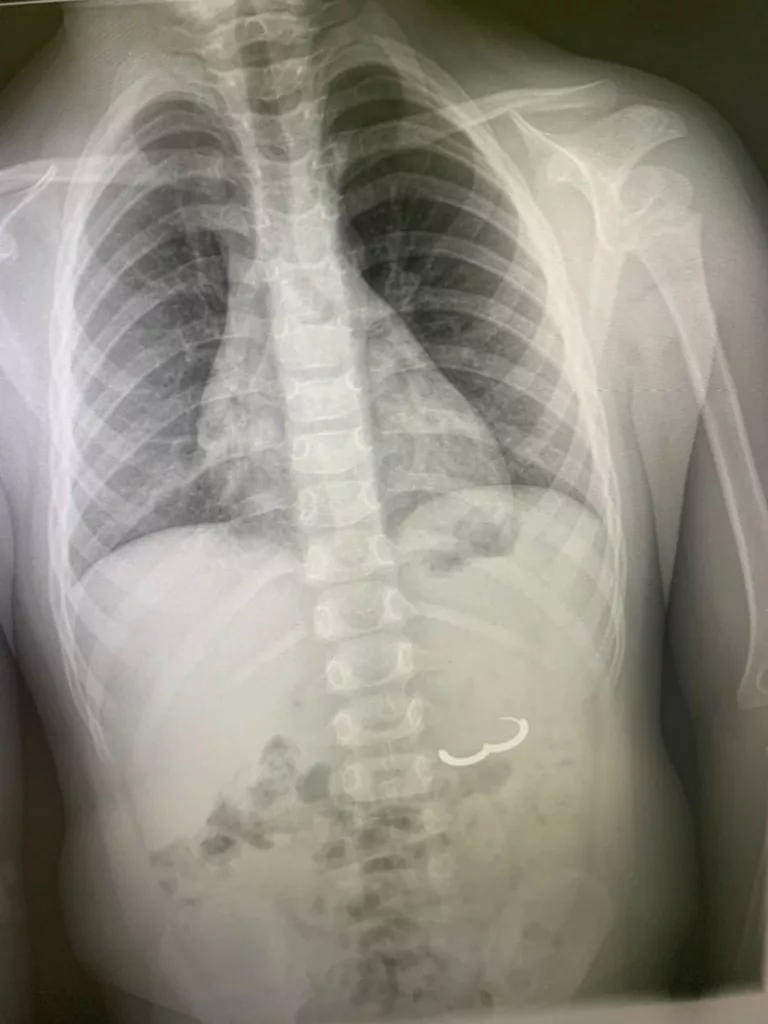

Безоперационное извлечение проглоченного предмета провели врачи эндоскопического отделения.

«Благодаря новому оборудованию и профессионализму наших сотрудников удалось провести процедуру извлечения инородного тела без хирургического вмешательства, — рассказал заведующий отделением эндоскопии ТРБ № 1 Гор Саакян.

— Оказалось, четырехлетний мальчик проглотил серьгу. К сожалению, такое часто бывает — дети часто тащат в рот блестящие маленькие предметы, поэтому родителям особенно важно исключать наличие мелких вещей в пределах доступности».

Сейчас состояние маленького пациента удовлетворительное, драгоценность тоже возвращена в семью.